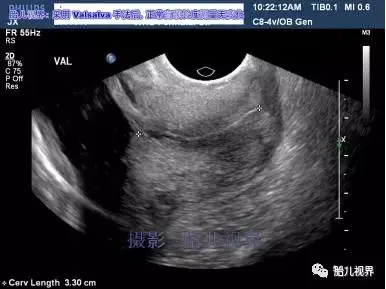

宫颈长度的超声检查

图片尺寸640x480